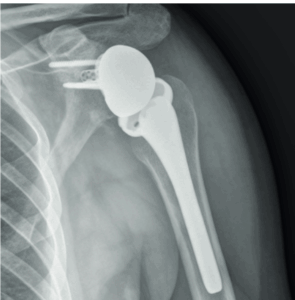

It was demonstrated that, despite the different concave shape of the glenoid, its OCD follows the same progression over the time of the convex weight-bearing articular surfaces and needs, likewise, the same gradespecific management. Patients with IRCS OCD stage I and some with OCD stage II present with a stable shoulder and can undergo conservative treatment. Unstable or advanced glenoid OCD stages, characterized by disruption of the articular cartilage and the presence of separated fragments as loose bodies, require surgical treatment. Moreover, this is indicated when the conservative approaches fail, especially because of long-standing pain and joint range of motion worsening. Proposed surgical treatments include arthroscopic drilling, microfractures, debridement of the unstable osteochondral fragments, and fixation with suture anchor or autogenous osteochondral plugs, platelet-rich plasma, and gellike sodium hyaluronate. (2,4) There is not yet consensus regarding the ideal technique. In this Technical Note, we describe an arthroscopic procedure with a single-layer hyaluronate-based scaffold for the treatment of OCD of the glenoid.